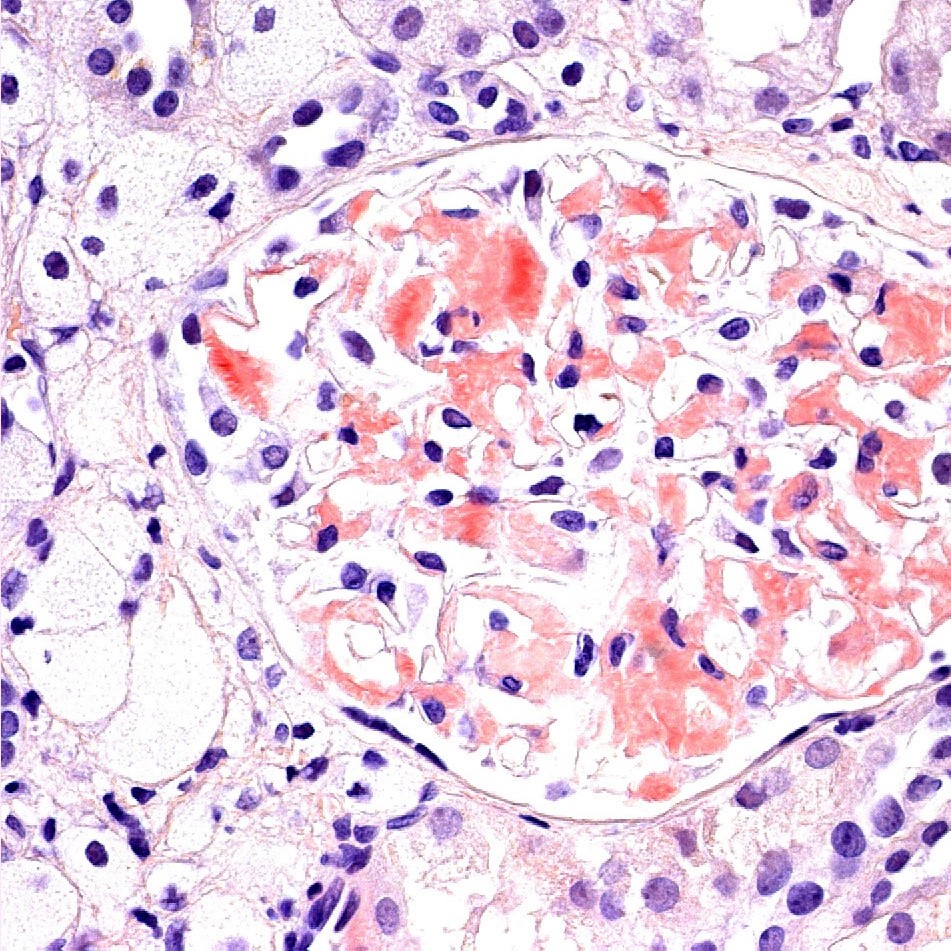

Le kit Congo Red Highman est utilisé pour la coloration des amyloïdes (amas amorphes). Les dépôts amyloïdes sont colorés de façon caractéristique en rouge, mais sous lumière polarisée, ils présentent une double réfraction et fournissent une coloration verte.

Dépôts amyloïdes - rose à rouge ; vert sous lumière polarisée

Noyaux - bleu